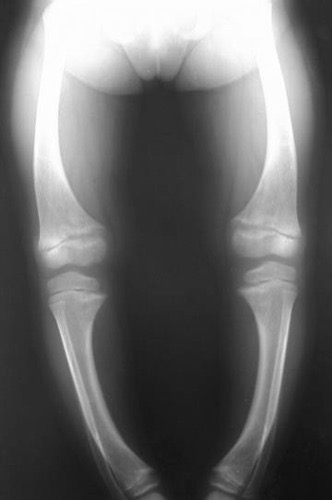

Tibia is an example of what type of bone?

long bone

Rickets

A bone weakness disease caused by vitamin D deficiency. Causes bone to bend or bow